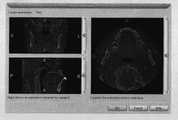

Figure 23 is slice view window again.

Figure 24 is virtual plantation sketch map.

5.2 registration

The registration tool of utilizing Geomagic software to provide can be adjusted the relative position of each model, utilize manual log-in command, the mandibular bone model of selecting the generation of CT data is as fixed target, the lower tooth triangle grid model that will be produced by cloud data is got the several characteristic point at both corresponding location points and is carried out registration as floating target.The upper tooth triangle grid model registration that uses identical method that the last dental cast and the cloud data of CT reconstruction are rebuild, as shown in figure 28.Make the relevant position alignment, should note the relative position of (a) CT threedimensional model model and tooth jaw plaster model during registration; (b) relative position of implantation body and mucosa; (c) relative position of implantation body and upper tooth.The scheme of implantation body's planning is reasonable behind the registration as can be seen, as Figure 29 (a)-(c).